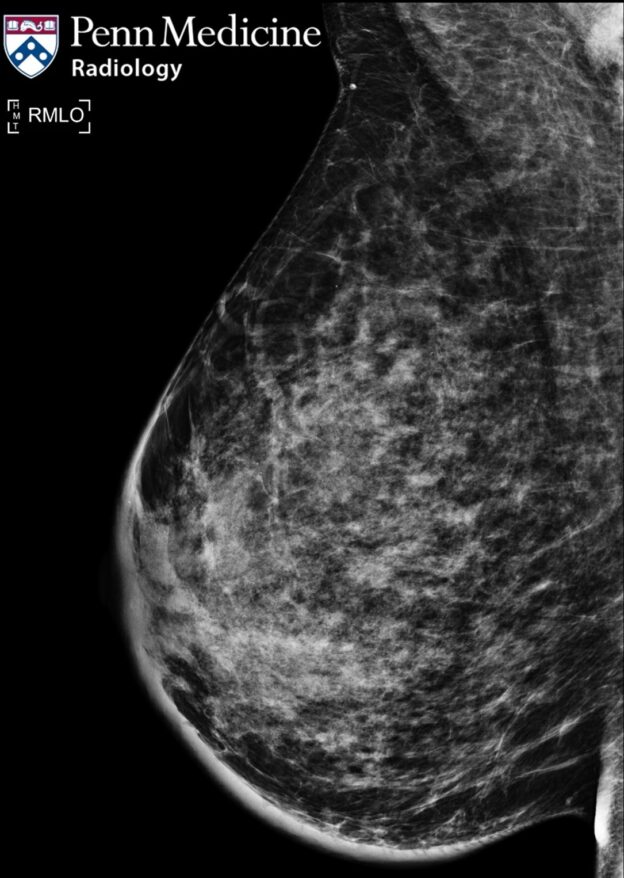

35-year-old woman with breast enlargement, tenderness, and erythema

A 35-year-old woman presented with enlargement, tenderness, and erythema of the right breast, more pronounced in the upper outer quadrant.